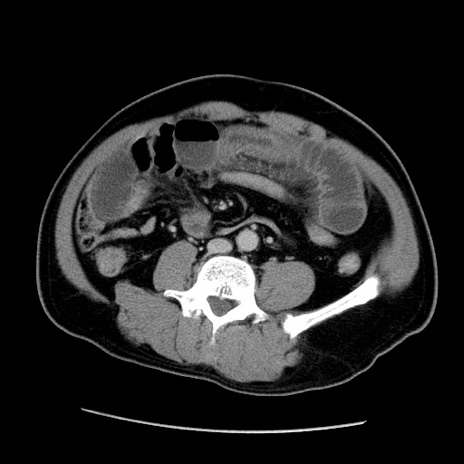

症例22(横断像)

【症例】50歳代男性

【主訴】腹痛

【現病歴】AVMからの被殻出血のため回復期リハ病棟入院中。 本日午後3時頃急に下腹部痛が出現した。

【既往歴】AVM、被殻出血、虫垂炎、高血圧

【身体所見】意識晴明、左半身不全麻痺、会話の理解は良好、36.5°C、腹部:膨隆、全体に板状硬、下腹部正中に圧痛点あり、反跳痛-、筋性防御不明、右下腹部にope scar

【データ】WBC 9400、CRP 0.06